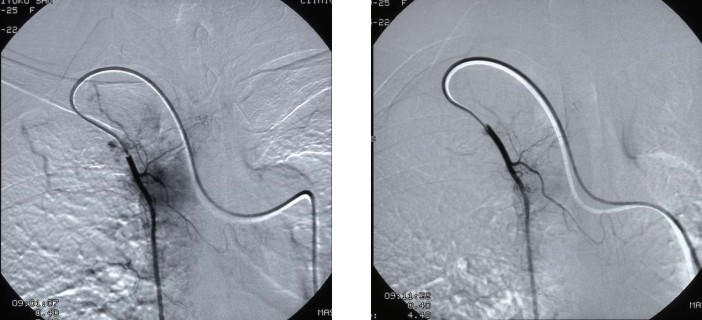

病例4 乳腺癌 stage IIIA

A 治疗前DSA示乳腺病灶 B 微血管介入后立即造影瘤染色消失

C 治疗前DSA D 治疗后3个月见病灶消失